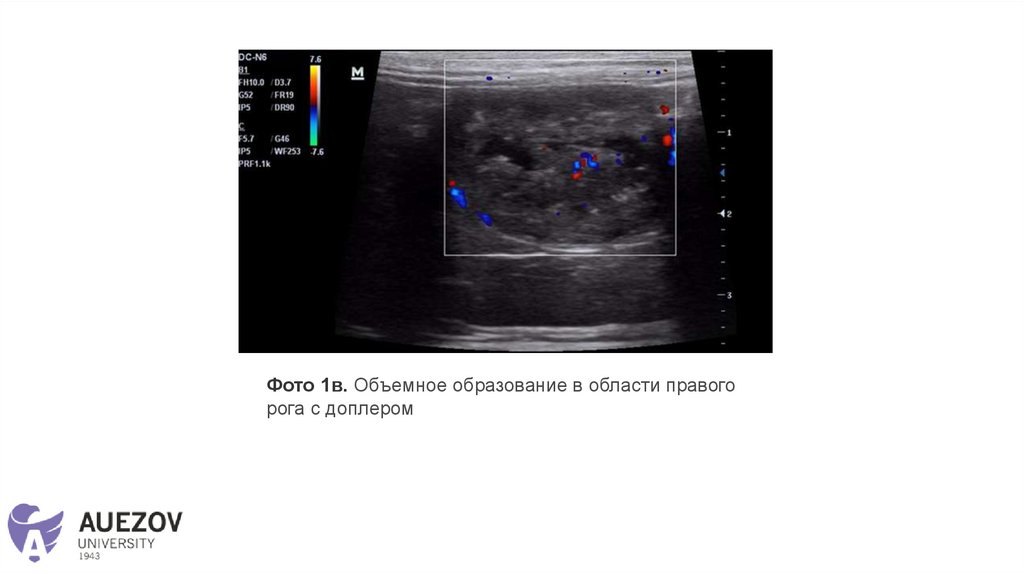

Фото 1в. Объемное образование в области правого

рога с доплером

В области правого рога визуализируется объёмное образование размером

2,9*2,3 см, неоднородное, гиперэхогенное с анэхогенными полостями

(жидкостное содержимое с гипоэхогенной взвесью), границы четкие,

контуры ровные, васкуляризация умеренная.